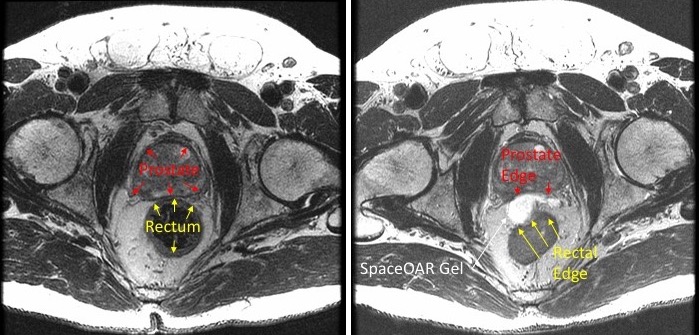

For patients who are susceptible to complications, Cooley uses a relatively new technique to move the rectum away from the treatment area to reduce the likelihood that the rectum will be exposed to radiation during treatment. He injects a substance called SpaceOAR into the space between the patient’s prostate and rectum, which pushes these two organs apart by about 1 cm and solidifies into a soft hydrogel that remains stable for three months.

The injection is a minor procedure that takes about five minutes and is usually done with the patient mildly sedated. Use of SpaceOAR poses virtually no risk to the patient and eventually passes from the body naturally.